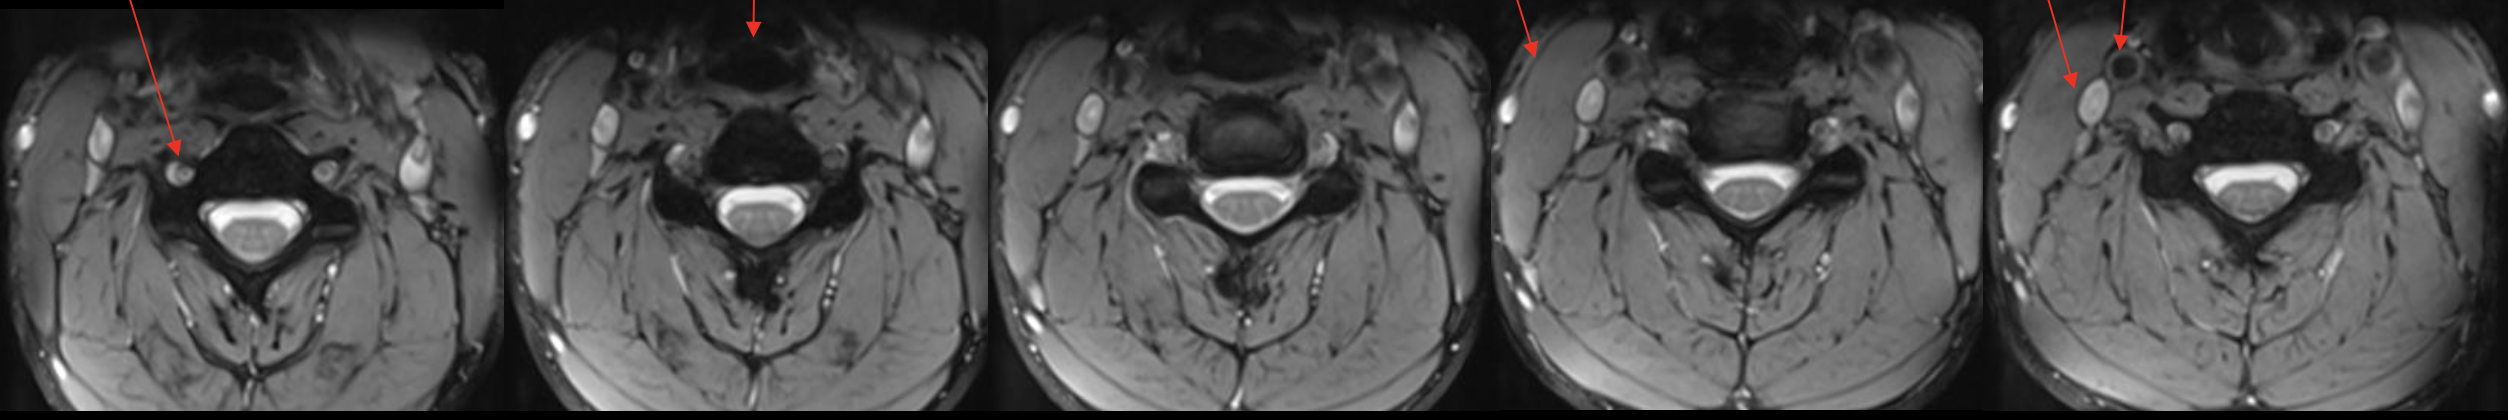

椎动脉

Vertebral artery

气管

Trachea

胸锁乳突肌

Sternocleidomastoid

颈内静脉

Jugular vein

颈动脉

Carotid artery